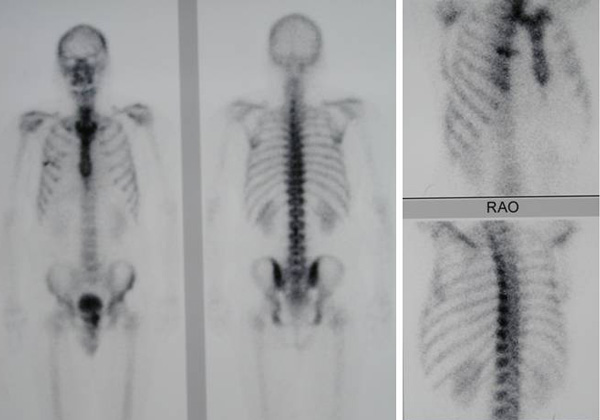

Bone scan on 2 June 2010 showed a mildly increased tracer activity in the mid to lower cervical spine, T4 and T5 vertebrae. No conclusive scan evidence of bone metastasis.

A bone scan was also performed on 6 October 2010.